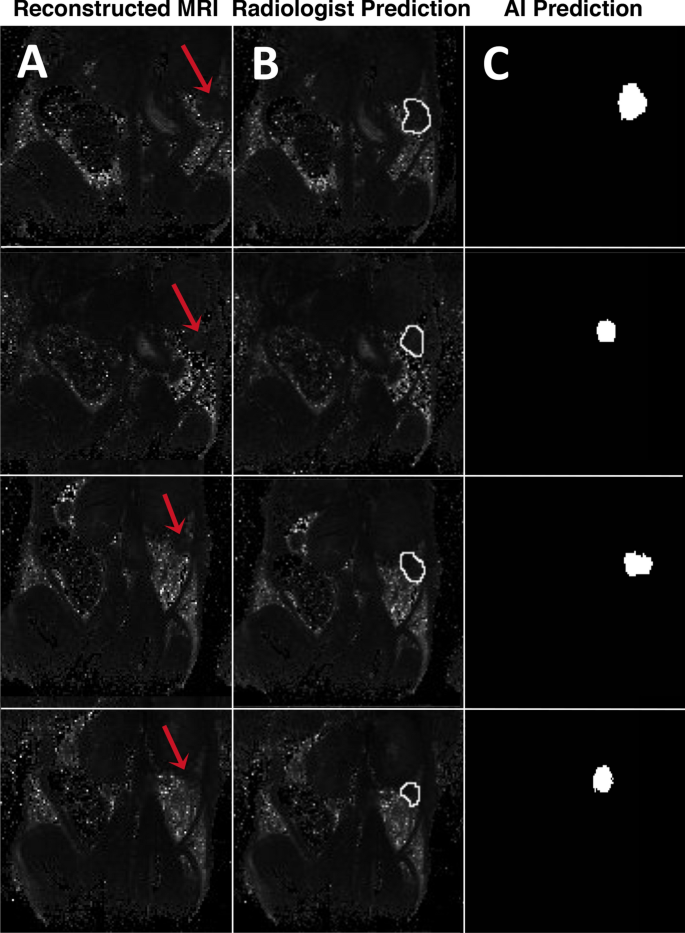

Figure 6 depicts a few of the several tumor ROI predictions by the two raters: the radiologist and the deep learning neural network. Reconstructed T2 maps from docetaxel treated groups are presented in Fig. 6A, as well as ROI of both treated and untreated groups predicted by raters (Fig. 6B,C). The level of agreement amongst their predictions was calculated using the ICC cross validation in SPSS statistical software.

Representative visual example of MR images used for ICC cross validation between the board-certified radiologist prediction and the deep learning algorithm prediction. (A) Original reconstructed MR image. (B) Prediction of tumor ROI labeled by a board-certified radiologist. (C) Prediction of tumor ROI by the deep learning algorithm segmentation.

Table 1A and B summarize Intraclass Correlation Coefficient (ICC) between the predictions of the two raters: the board-certified radiologist and the deep learning algorithm. Ordinarily, acceptable ICC scores range between 0.7 and 0.9, with the score greater than 0.9 considered excellent. It can be seen from Table 1A and B that there is a greater degree of correlation and agreement amongst the predictions of tumor ROI sum (size) than the ICC for tumor circularity between the two raters, as indicated by the single measure values 0.890 and 0.856 for tumor size and shape, respectively. This is likely due to the degree of error that is introduced when contouring the tumor manually, frequently leading to minor discrepancies in the shape of the tumor prediction, which is often remediated by the prediction of tumor size between the two raters. That is, the exact shape of the tumor may differ amongst radiologists and the artificially intelligent neural network, however, the ROI size and total number of pixels remains relatively constant. The latter value is of greater importance than tumor shape when preforming tumor analysis such as calculating deltaT2 values between different images and measuring relative probe accumulation in response to chemotherapy. Therefore, it can be validated from the ICC score that there is a high degree of interrater reliability between the AI and board-certified radiologist in regard to segmentation of the proper tumor ROI from a negative contrast pixel field of the reconstructed MR image.